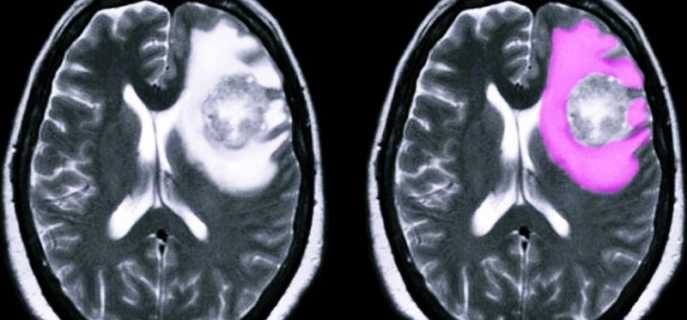

- Опухолевые процессы (рак), в частности глиобластома и киста, локализованные в различных отделах мозга, которые приводят к проблемам с оттоком ликвора или смещению структур мозга.

Чаще всего у людей бывает вазогенный отек, который начинает развиваться на фоне увеличения уровня проницаемости гематоэнцефалического барьера. Важный патологический процесс при этом заболевании – переход жидкости из сосудов в белое вещество мозга. Отечность в этом случае обычно начинает появляться в месте опухолевого процесса, ишемии, зоне проведения операции или абсцессных проявлений.

Для диагностики заболевания используются различные современные методы: МРТ, КТ, УЗИ и многие другие. Если форма патологии не молниеносная, то заподозрить наличие заболевания может невролог, который отметит прогресс ухудшения состояния больного, наращивание процессов нарушения сознания вместе с симптоматикой менингита.

Чтобы подтвердить диагноз, используются методы магнитно-резонансной и компьютерной томографии.